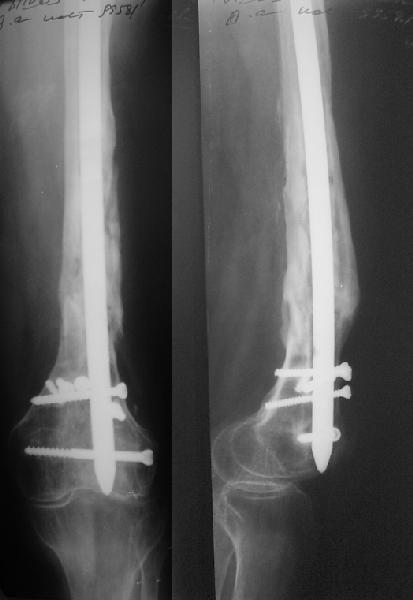

В 2002 г. была у нас больная с ложным суставом бедра и остеомиелитом (как оказалось), после удаления пластины. Гвоздь с блокированием.

Потекло через месяц - открылось 2 свища по старому рубцу от давно удаленной пластины. На фоне гноя раза три завинчивал обратно винты, которые вылезали латерально, прямо через свищ. Потом таки провел дополнительно винты мимо гвоздя, и убрал вверху статический винт. Острый гнойный процесс стих, свищи мыла она дома дважды в день водным хлоргексидином, ходила с возрастающей нагрузкой, а к 10 мес. и свищи закрылись, и срослось. Итоговые снимки от 18 апреля 2003 г. прилагаю.

Выполненный остосинтез нестабилен. Штифт надо заменить по "размеру" на солидный, дистльно три запирающих винта. Успехов!

Перелом спиральный, то есть низкоэнергетический, так что со сращением дело обстоит уже неплохо, лишь бы "костоеда" не развилась. Отломки выглядят уже стабилизированными костной мозолью, так что довводить винты, наверно, уже незачем. Разве что при клинической оценке подвижность еще есть - тогда можно для стабилизации наложить простейший аппарат, не опасаясь контакта его элементов с гвоздем, поскольку места в дистальном метафизе оставлено более чем достаточно.

С Александром согласен, нет необходимости делать дополнительные усилия для сращения, не большая компрессия аппаратом из двух колец и полная нагрузка доделает работу.